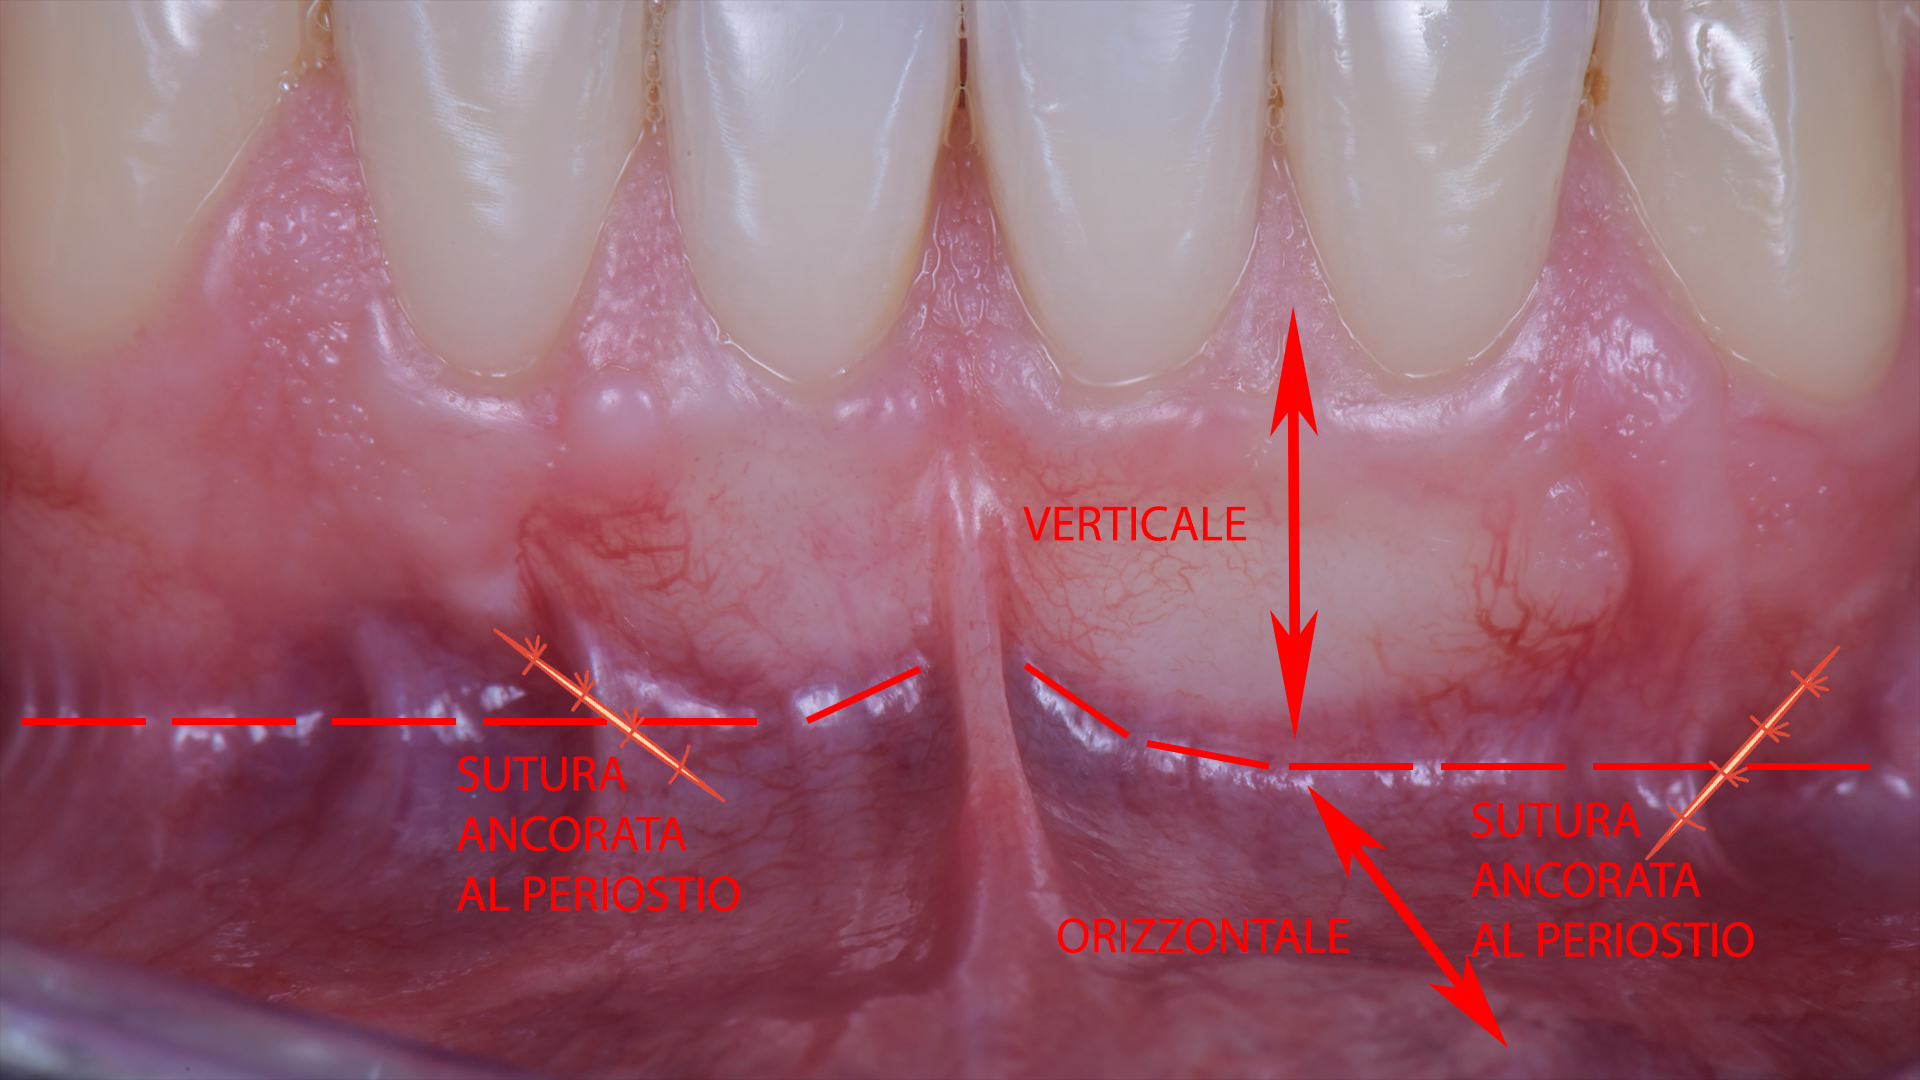

Ovviamente questa oggi non ci serve a nulla perché gestendo bene il muscolo come abbiamo già imparato non dobbiamo rompere nessuna forza, ma dobbiamo trasformare un lembo che è diventato completamente orizzontale in un lembo verticale che cambia direzione dove vogliamo che partano le nuove inserzioni muscolari.

Per fare questo basta iniziare a suturare proprio in quel punto, prima su uno scarico verticale e poi sull’altro, ancorando i punti al periostio del tessuto non mobilizzato laterale. Ovviamente mantenedo il lembo nella posizione finale con le pinzette.